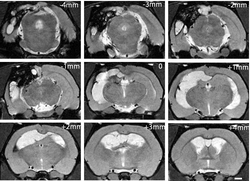

Our research program aims to understand and harness the tumor microenvironment to study and treat triple negative breast cancer and glioblastoma. We design and use 3D tissue engineered models based on patients' cancers and validate our work in vivo. Our primary questions in cancer include the role of tissue drainage and the tumor stroma in cancer progression and therapeutic response. We collaborate extensively with the School of Medicine to make our research translational and applicable to patients with cancer.